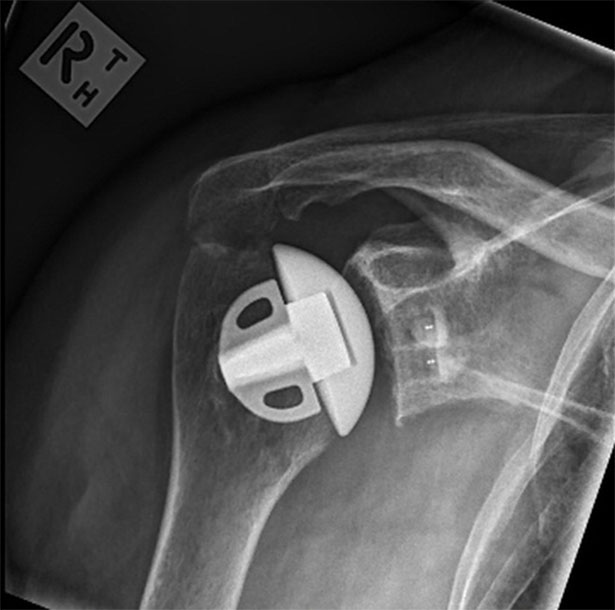

Shoulder after replacement surgery

Move the slider to compare arthritic shoulder with stemless replacement